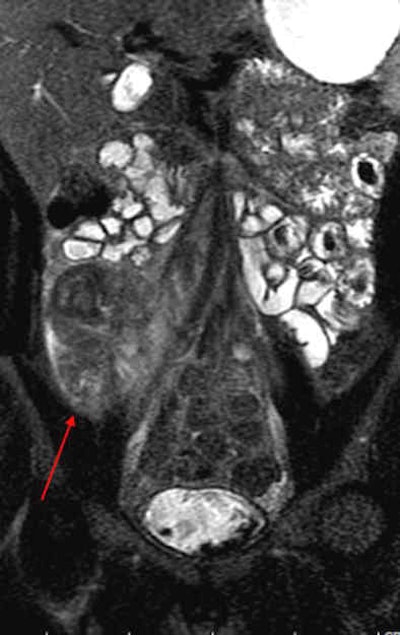

MRI results were then compared to colonoscopy and pathology reports to determine the presence or absence of disease in evaluable bowel segments. Individual imaging parameters (including wall thickening, enhancement, T2 signal, mesenteric vascular prominence, and adenopathy) were also separately analyzed to determine their independent predictive value, the authors wrote.

The study team acquired steady-state free-precession (SSFP) images of the abdomen and pelvis (TR= 4 ms, TE = 2 ms, slice thickness 8 mm for coronal images and 8-mm for axial images). Axial and coronal fat-suppressed half-fourier single-shot fast-spin echo (SSFSE) and axial spoiled-gradient images were also obtained through the abdomen, followed by T1-weighted fat-suppressed spoiled-gradient echo (LAVA/VIBE) images, before the injection of 1 mmol/kg of gadopentate dimeglumine contrast (Bayer Healthcare) followed by a saline flush and postcontrast imaging.

A single experienced abdominal radiologist, blinded to the final results, interpreted all of the MRE images, rating wall thickness, abnormal enhancement, abnormal T2 signal, and mesenteric vascular prominence on a scale of 1-4. All endoscopy reports were reviewed for mention of inflammatory changes in specific bowel segments, and pathology reports were reviewed for the presence of inflammatory disease, the study team reported.

Interestingly, the results were in line with smaller studies that used antiperistaltic agents, they wrote. As in those studies, MRE showed its real strength in a couple of features of active Crohn's disease. "Analysis of individual MR parameters demonstrates that wall thickening and abnormal enhancement are the most sensitive indicators of Crohn's disease on MRE while abnormal T2 signal, mesenteric vascular engorgement, and adenopathy were insensitive but specific," he wrote.